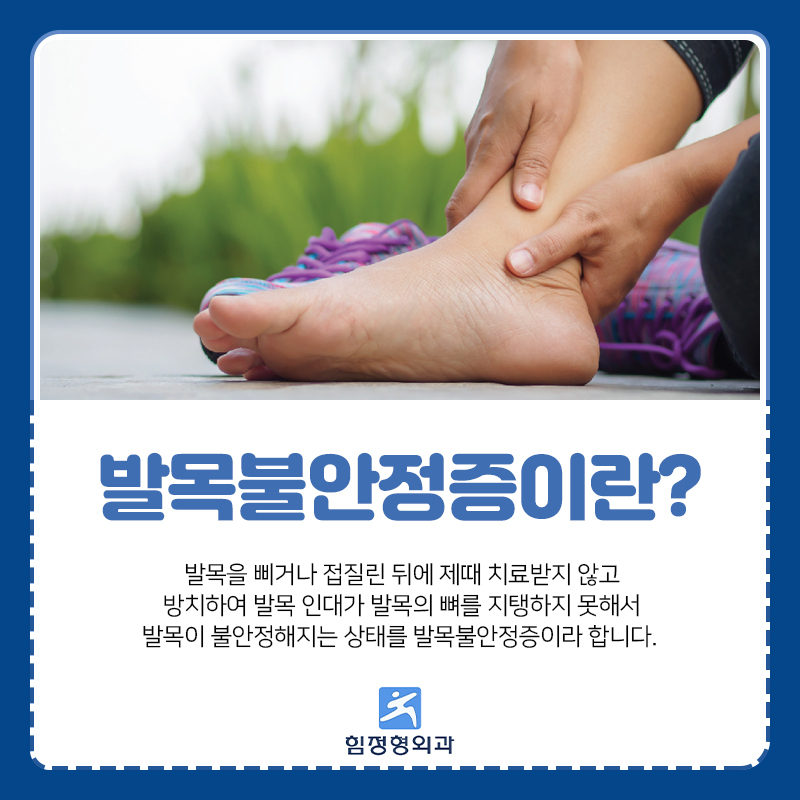

발목불안정증이란 ?

발목불안정증은 발목을 사용하게 될때 접지르게 된 후

치료를 오랫동안 받지 않고 방치를 하게 됭서ㅓ

지탱하고 있는 기능이 떨어지게 되는 경우를 말합니다.

지속적으로 같은 증셍들이 반복하게 되며,

제대로 이 질환을 치료 하지 않는 경우에는

발목 관절염으로 발전할 수 있습니다.